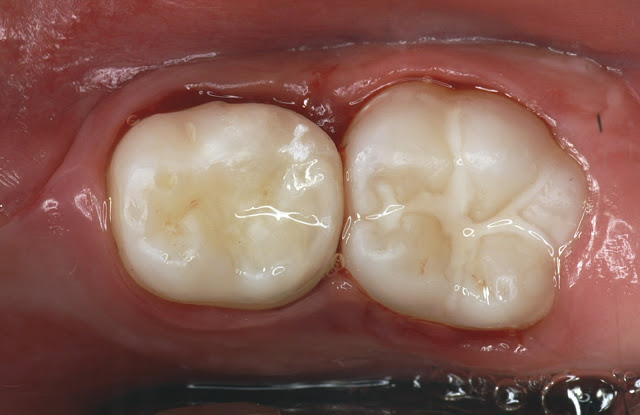

Restorative dental materials are designed to replace or repair damaged tooth structure, restoring both function and esthetics. The choice of material depends on clinical requirements, tooth location, functional demands, and patient preferences.

• Composite Resin: Tooth-colored, versatile, ideal for anterior and posterior restorations.

• Glass Ionomer Cement (GIC): Releases fluoride and bonds chemically to tooth structure; suitable for non-load-bearing restorations.

• Resin-Modified Glass Ionomer Cement (RMGIC): Combines the benefits of GIC (fluoride release and chemical bonding) with enhanced strength, wear resistance, and esthetics due to added resin. It is suitable for small to moderate restorations, cervical lesions, and as a base/liner under composites